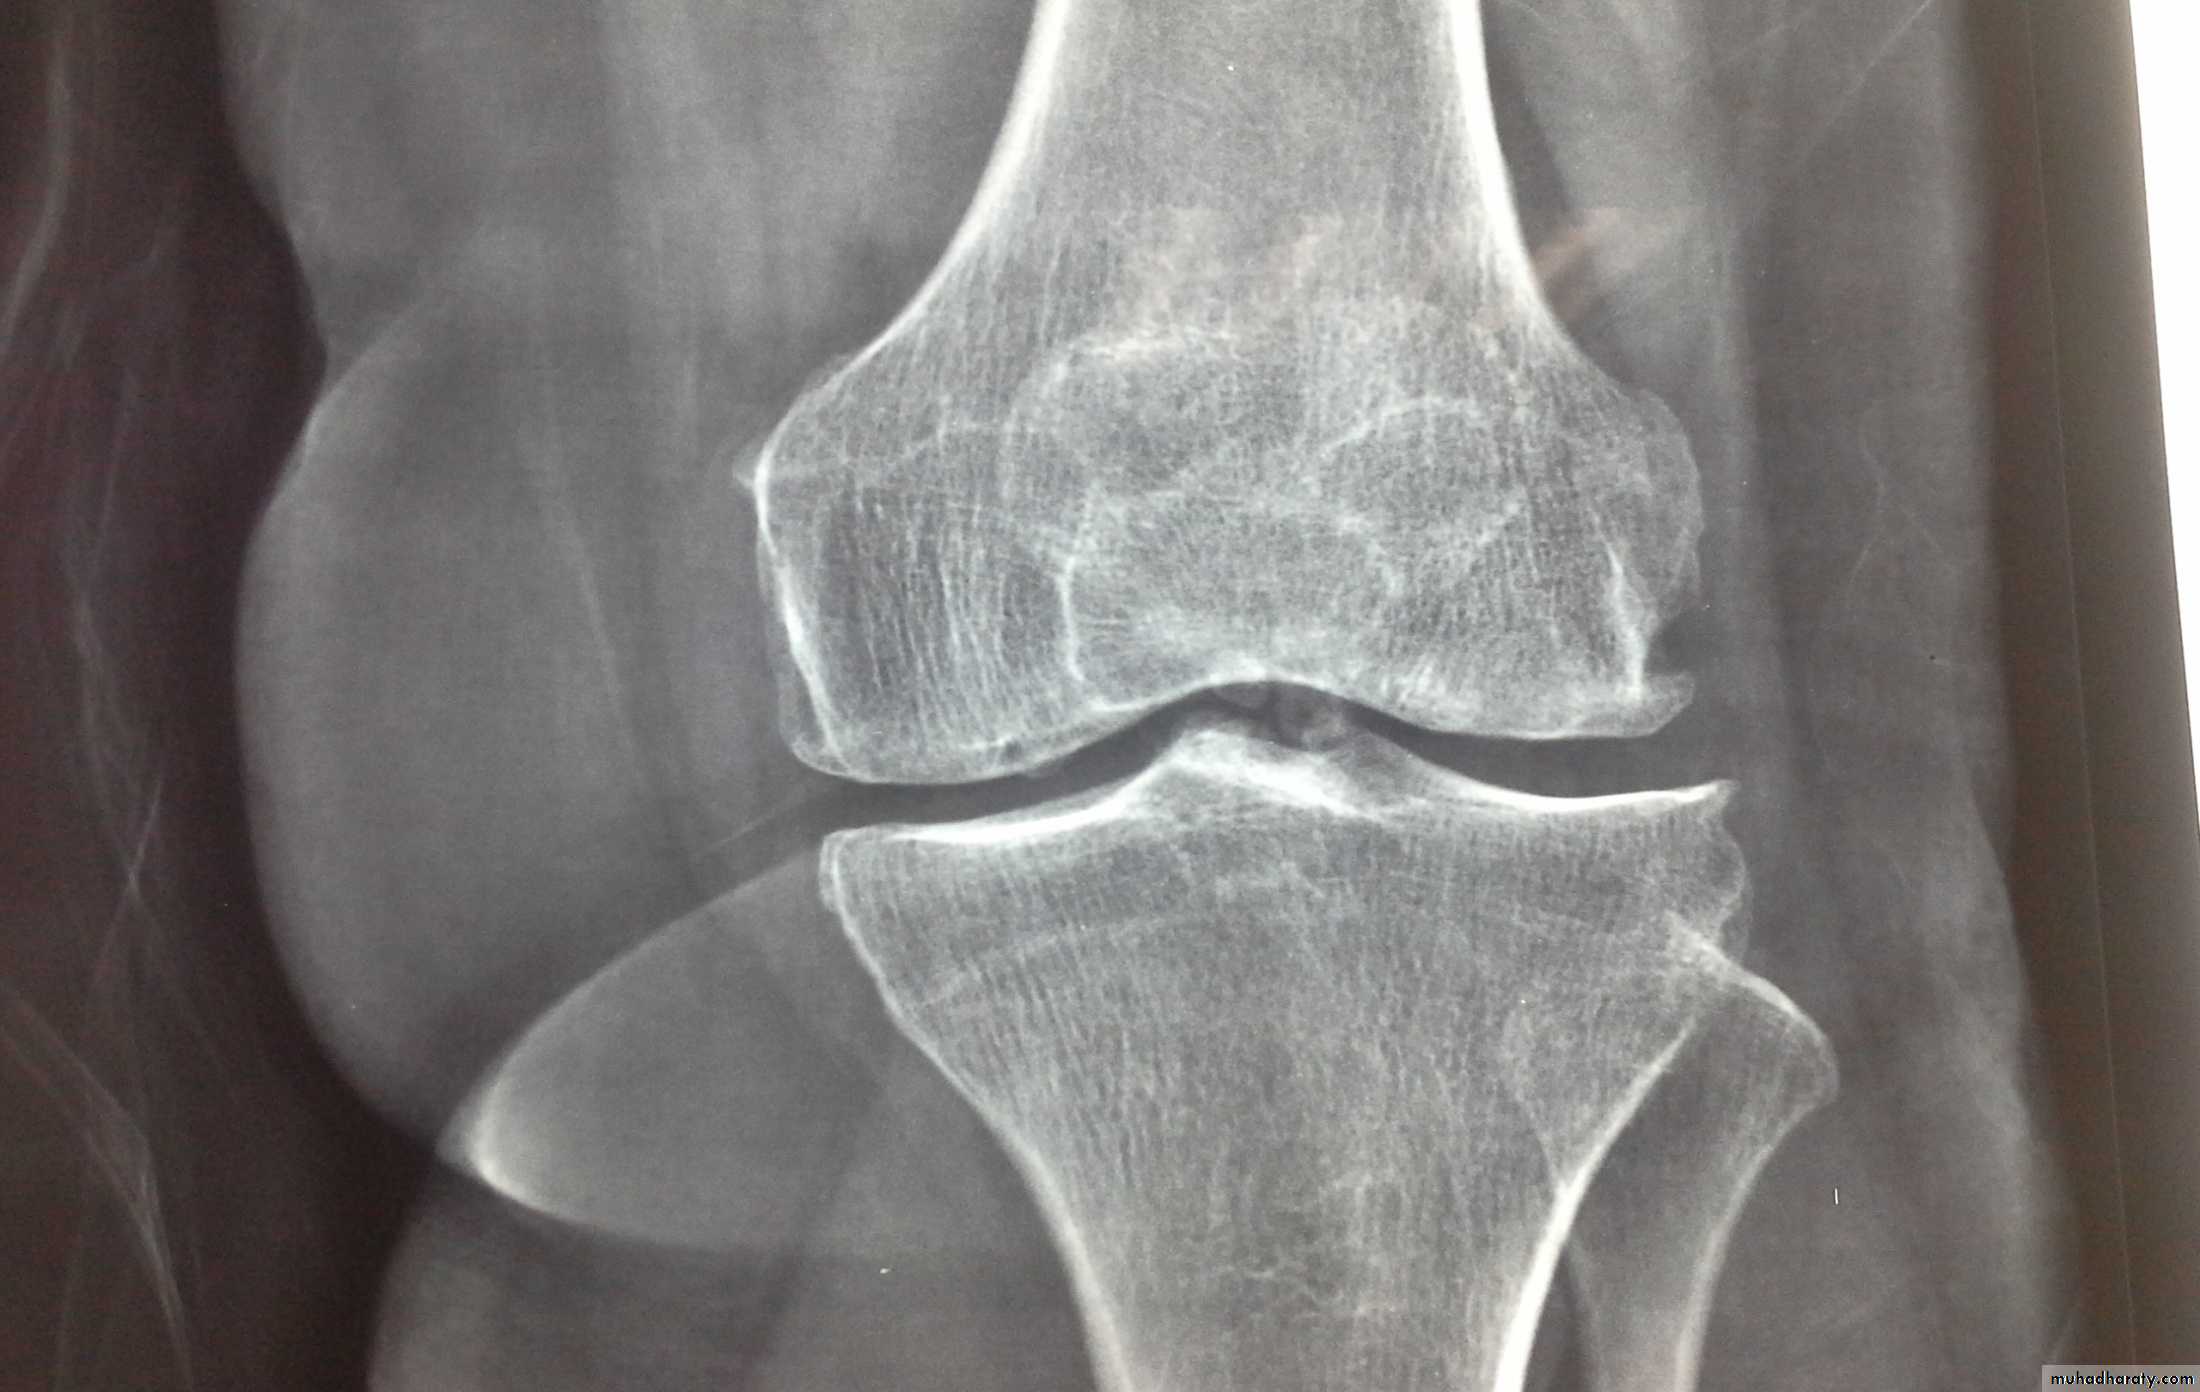

Chronic Pyrophosphate Dihydrate(CPPD)crystal deposition

-CPPD crystal deposition in hyaline and fibro-cartilage of joints( Chondrocalcinosis) is a common age associated phenomenon affects the knee and can cause self limiting synovitis (pseudogout) or chronic arthritis and showing astrong association with nodal OAChronic Pyrophosphate Dihydrate(CPPD)crystal deposition

-it is rare under the age of 55- the knee,wrist, and symphysis pubis are the most common prevelent sites

chondrocalcinosis

2- radiographs: show chondrocalcinosis with or without OA3- secreening for familial or metabolic predisposing factors in patients with :a-early onset disease(under 55 years old)b-polyarticular diseasec-recurrent acute attacksd- clinical or x-ray finding of predisposing disease